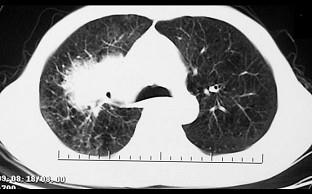

问题 男,68岁,右侧胸痛伴右上臂麻木一周,胸部CT、MRI扫描如图,最可能的诊断为 ( )

选项 A、右上肺中央型肺癌并右上肺不张,纵隔淋巴转移 B、右上肺周围型肺癌并纵隔淋巴转移 C、右上肺肉瘤并纵隔淋巴转移 D、右上肺不张 E、右上肺硬化性血管瘤

答案 A